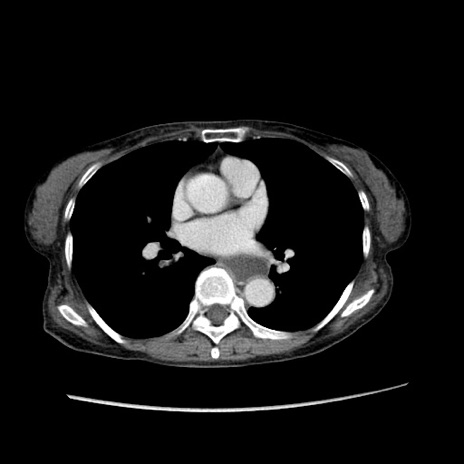

症例25(横断像)

【症例】80歳代女性

【主訴】胸のつかえ感

【現病歴】約9時間前に食後から胸のつかえた感じあり、嘔吐あり、来院。

【既往歴】胃癌(全摘)、胆摘、虫垂炎

【身体所見】心窩部に圧痛あり、反跳痛なし。

【データ】WBC 5700、CRP 0.05